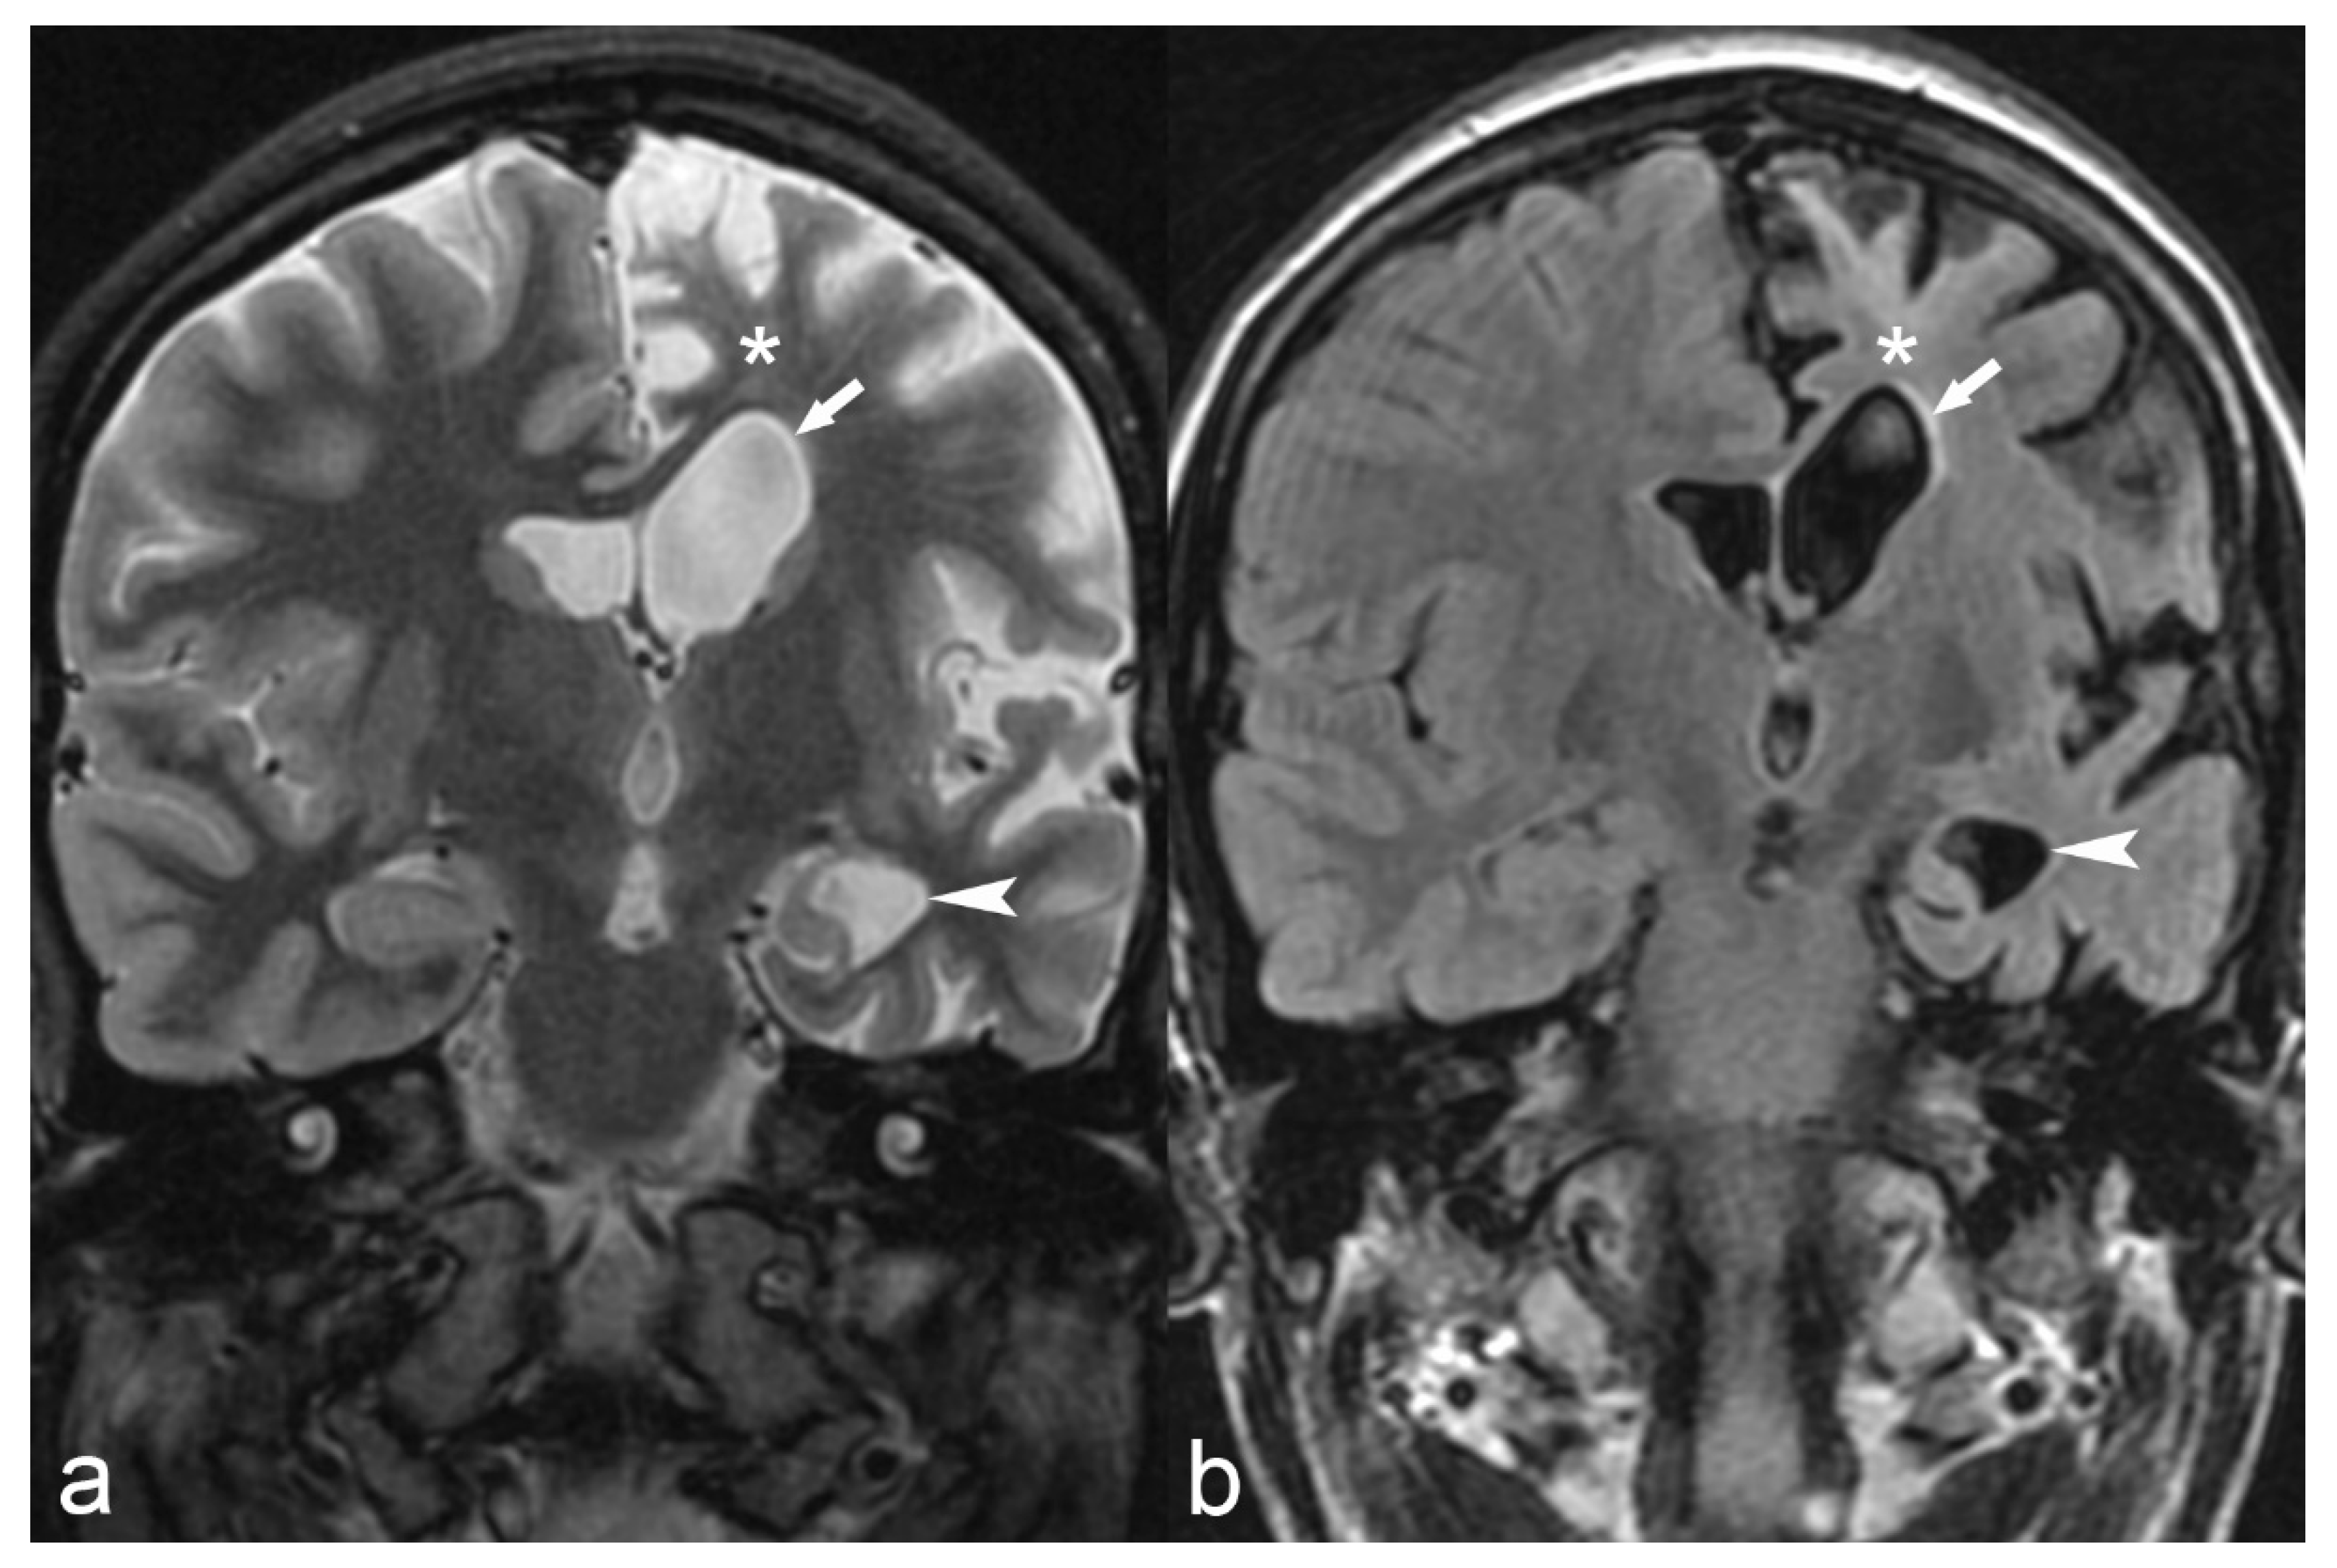

Figure 4.

36-year-old woman. The right hippocampus is smaller than the left (arrows) as seen on coronal T2WI (a), FLAIR (b) and MP2RAGE (c) and shows hyperintensity on T2WI and FLAIR. There is also flattening and loss of the normal undulations of the right hippocampus, suggestive of hippocampal sclerosis.